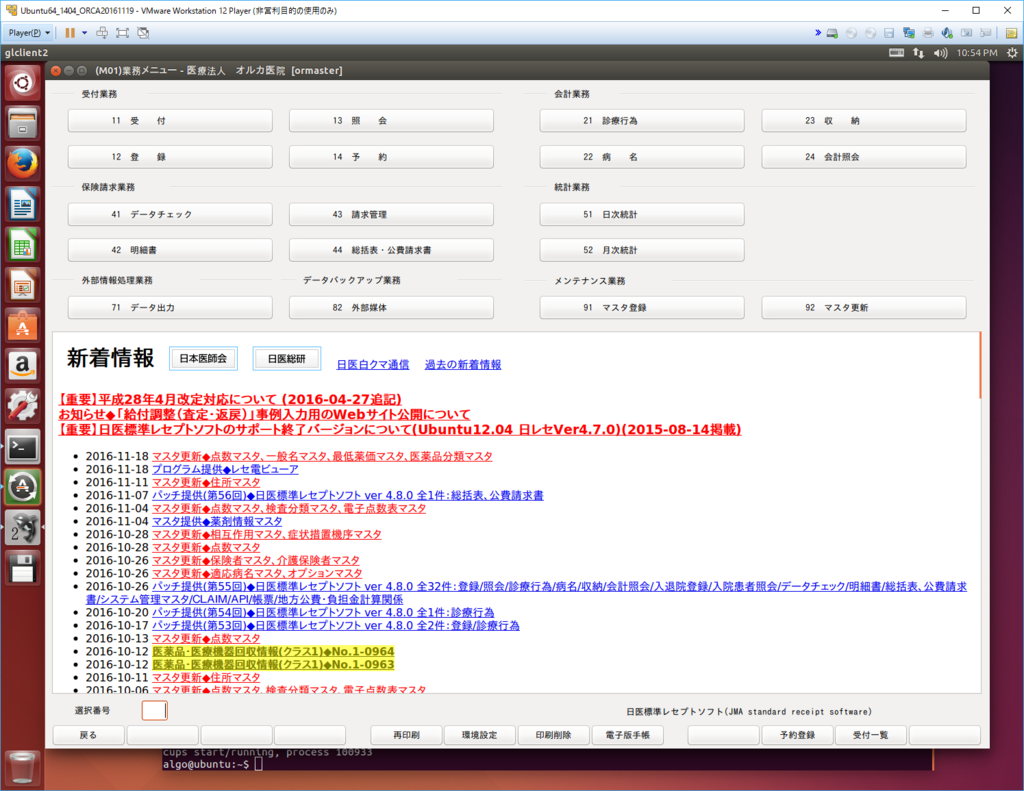

接続すると

上手く起動しました。

ORCAデータの定期的バックアップと、復元方法をマスターしてしまえば、業者に委託せずとも管理できそうです。あとは医療事務さんの同意が得られれば、現在のシステムから移行できるかな…。